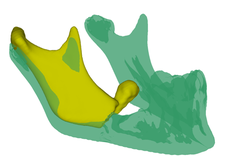

- Dzięki zastosowaniu modeli żuchwy wykonanych przy użyciu druku 3D, znacznie skrócono czas przeprowadzenia zabiegu chirurgicznego, a także zminimalizowano wystąpienie komplikacji śródoperacyjnych - wyjaśnia twórca modelu dr inż. Paweł Turek, adiunkt w Katedrze Technik Wytwarzania i Automatyzacji PRz. - Dodatkowo opracowano procedurę umożliwiającą komputerowe (wirtualne) odtworzenie geometrii żuchwy sprzed wystąpienia urazu.